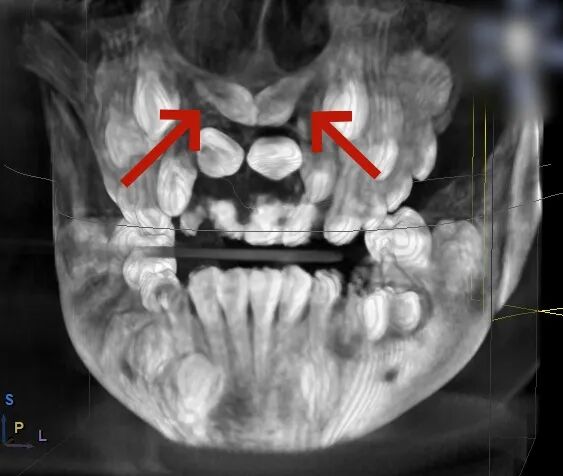

术前,医生通过 CBCT 扫描获取患者颌骨的精准立体影像,清晰定位埋伏牙的位置、形态以及与周围血管、神经的关系;随后在电脑上进行虚拟手术设计,规划出最佳的拔除路径,巧妙避开重要组织;最后通过3D打印技术,定制出完全贴合患者口腔结构的导板。这块小小的导板,就像是为手术钻头安装了“GPS导航”,能在术中精准引导器械方向,让拔牙过程变得微创、安全、高效。

牙支持式定位导板